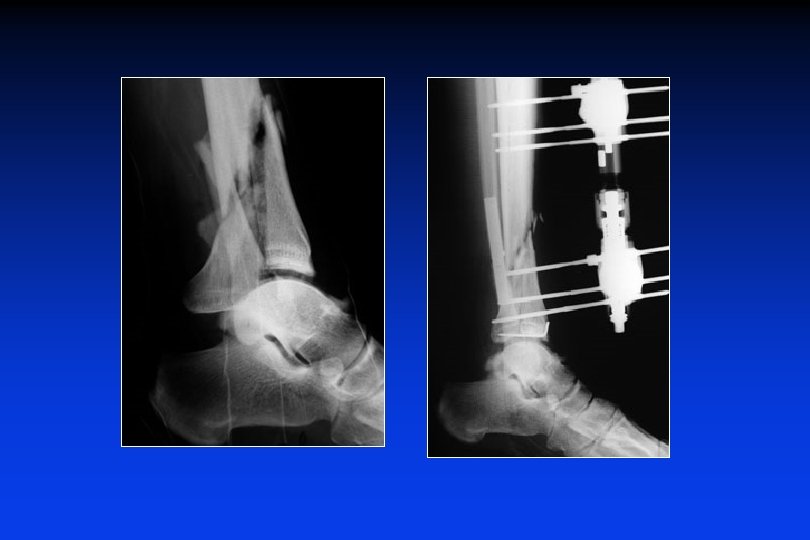

Consolidazione viziosa

Callo vizioso e sublussazione posteriore